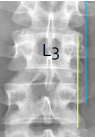

Q what is the name of this measurement? and what is the average + range?

A: Interpediculate Distance

assesses the shortest distance between the inner surfaces of the pedicles. 1.5-2mm